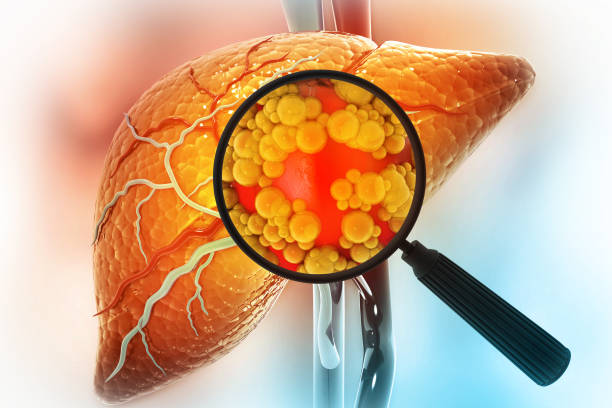

간경화 초기증상은 증상이 나타나지 않거나, 미미한 증상만 나타나기 때문에, 무시하고 지나치기 쉬운 경우가 많습니다. 하지만, 이러한 초기 증상을 간과하면 질병이 진행되어 치료가 어려워질 수 있습니다. 따라서, 간경화 초기증상을 발견하면 적절한 검사와 치료를 받아 조기에 질병을 예방하고 치료할 수 있습니다. 따라서 이번 시간에는 간경화 초기증상에 대해 자세히 알아보도록 하겠습니다.